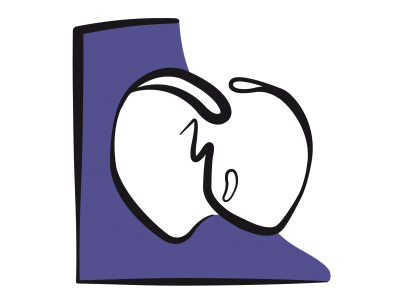

La fonction diastolique représente la capacité du ventricule à accommoder un remplissage adéquat sous un régime de pression basse et sur un vaste éventail de conditions de charge (voir Chapitre 5 La diastole). La dysfonction diastolique se réfère à une anomalie des indices échocardiographiques du remplissage ventriculaire qui reste cliniquement asymptomatique sauf à l'effort majeur, alors que l’insuffisance diastolique, responsable de près de 50% des insuffisances cardiaques congestives, est un syndrome clinique qui se caractérise par une dyspnée et une élévation chronique des pressions de remplissage (POG > 16 mmHg) en présence d’une fonction systolique préservée (FE > 0.5) [2,4]. Dans tous les cas, la pression télédiastolique ventriculaire est plus haute pour un même volume de précharge [2,7]. Une dysfonction diastolique est toujours présente en cas d’insuffisance ventriculaire systolique.

La fonction diastolique représente la capacité du ventricule à accommoder un remplissage adéquat sous un régime de pression basse et sur un vaste éventail de conditions de charge (voir Chapitre 5 La diastole). La dysfonction diastolique se réfère à une anomalie des indices échocardiographiques du remplissage ventriculaire qui reste cliniquement asymptomatique sauf à l'effort majeur, alors que l’insuffisance diastolique, responsable de près de 50% des insuffisances cardiaques congestives, est un syndrome clinique qui se caractérise par une dyspnée et une élévation chronique des pressions de remplissage (POG > 16 mmHg) en présence d’une fonction systolique préservée (FE > 0.5) [2,4]. Dans tous les cas, la pression télédiastolique ventriculaire est plus haute pour un même volume de précharge [2,7]. Une dysfonction diastolique est toujours présente en cas d’insuffisance ventriculaire systolique.